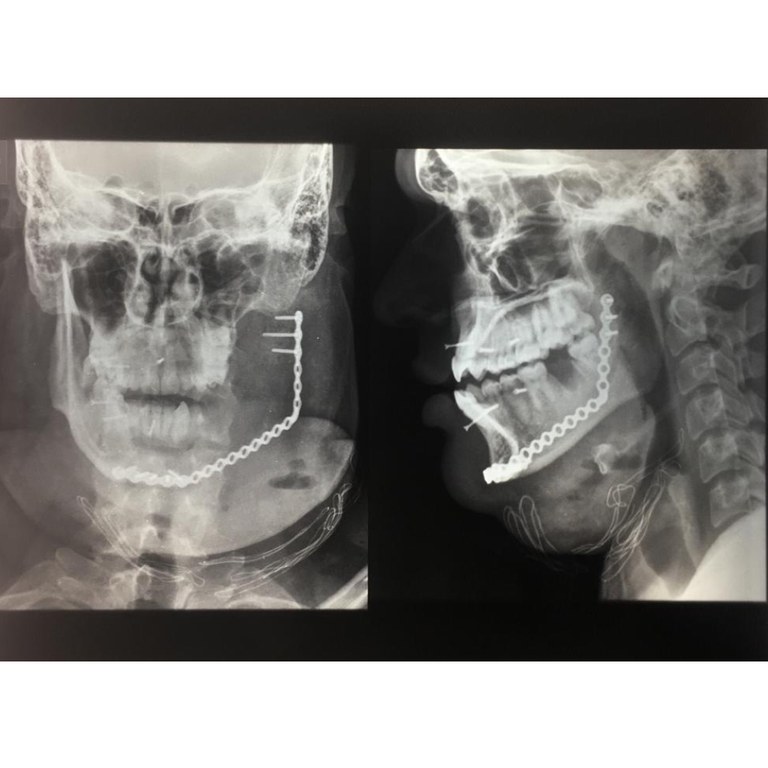

Primeiro biomodelo de órgão humano produzido pela UFPB facilita remoção de tumor em paciente